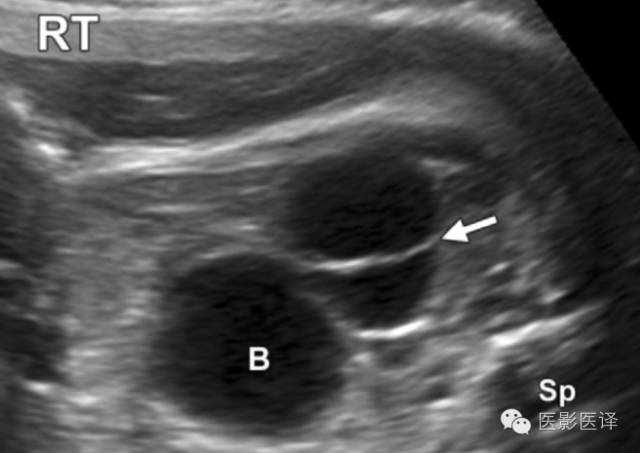

Nussbaum等最早将新生儿卵巢囊肿分为单纯性和复杂性。单纯性卵巢囊肿是圆的、无回声的、单房和薄壁的(图1)。它们更经常为单侧而非双侧、更经常为腹内而非盆腔内。单纯性囊肿内偶尔可见单个分隔(图2)。直径小于20mm的卵巢囊性结构被认为是成熟卵泡,为生理性而非病理性。直径大于20mm的囊肿则考虑为异常。“子囊”征描述的是囊内一个小的、圆形、无回声结构(图3)。既往报道认为这是卵巢囊肿的特征。【在一个23例囊性病变的研究中(包括新生儿、婴儿及儿童),11例发现子囊,占卵巢囊肿的82%(敏感度82%,特异度100%,阳性预测值100%),在其他囊性病变中未发现子囊,包括淋巴管瘤、肠重复畸形、肠囊肿、胎粪假性囊肿、阴道积液和脐尿管囊肿。】

图2:有单分隔的卵巢囊肿:轴位胎儿超声图像显示一个边界清楚有单一薄壁分隔的(箭)腹内囊肿。囊肿位于膀胱外侧,并在其他图像中显示独立于肾脏和胃肠道。超声多普勒图像(未展示)提示囊肿内无血管。RT=右侧,Sp=脊柱。